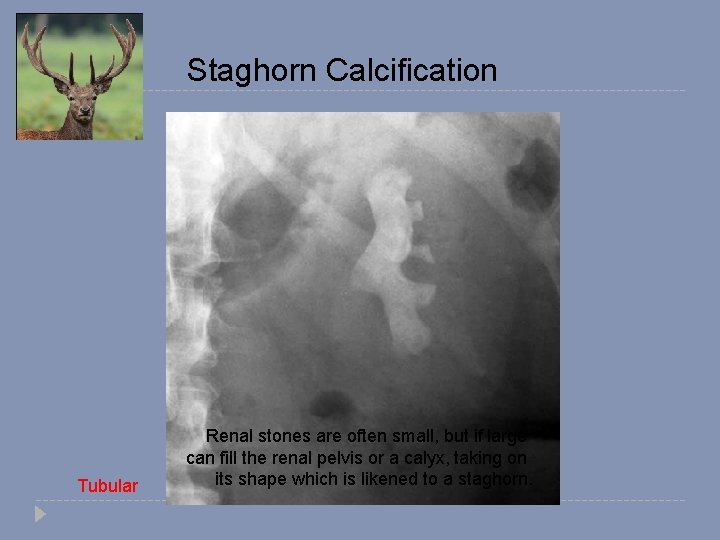

Staghorn Calcification Tubular Renal stones are often small, but if large can fill the renal pelvis or a calyx, taking on its shape which is likened to a staghorn.